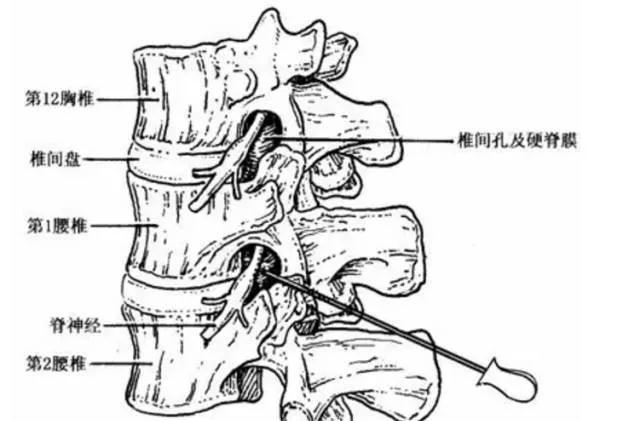

脊柱是由一块块带孔的骨头组合起来的,而这些带孔的骨头摞在一起,就形成了椎管。椎管里面主要走行的是脊髓,脊髓又分叉出很多神经根。这些神经根经过椎管两侧的椎间孔走出。

椎管的前壁由椎体后面、椎间盘后缘和后纵韧带构成,后壁为椎弓板、黄韧带和关节突关节,两侧壁为椎弓根和椎间孔。

(3)椎管造影:常在腰2,3椎间隙穿刺注药造影,此时可出现尖形中断,梳状中断及蜂腰状改变,基本上可了解狭窄全貌(图3),由于本检查属侵入式,目前已少用。